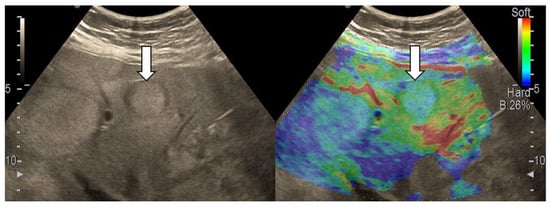

3.4. Real-Time Tissue Elastography